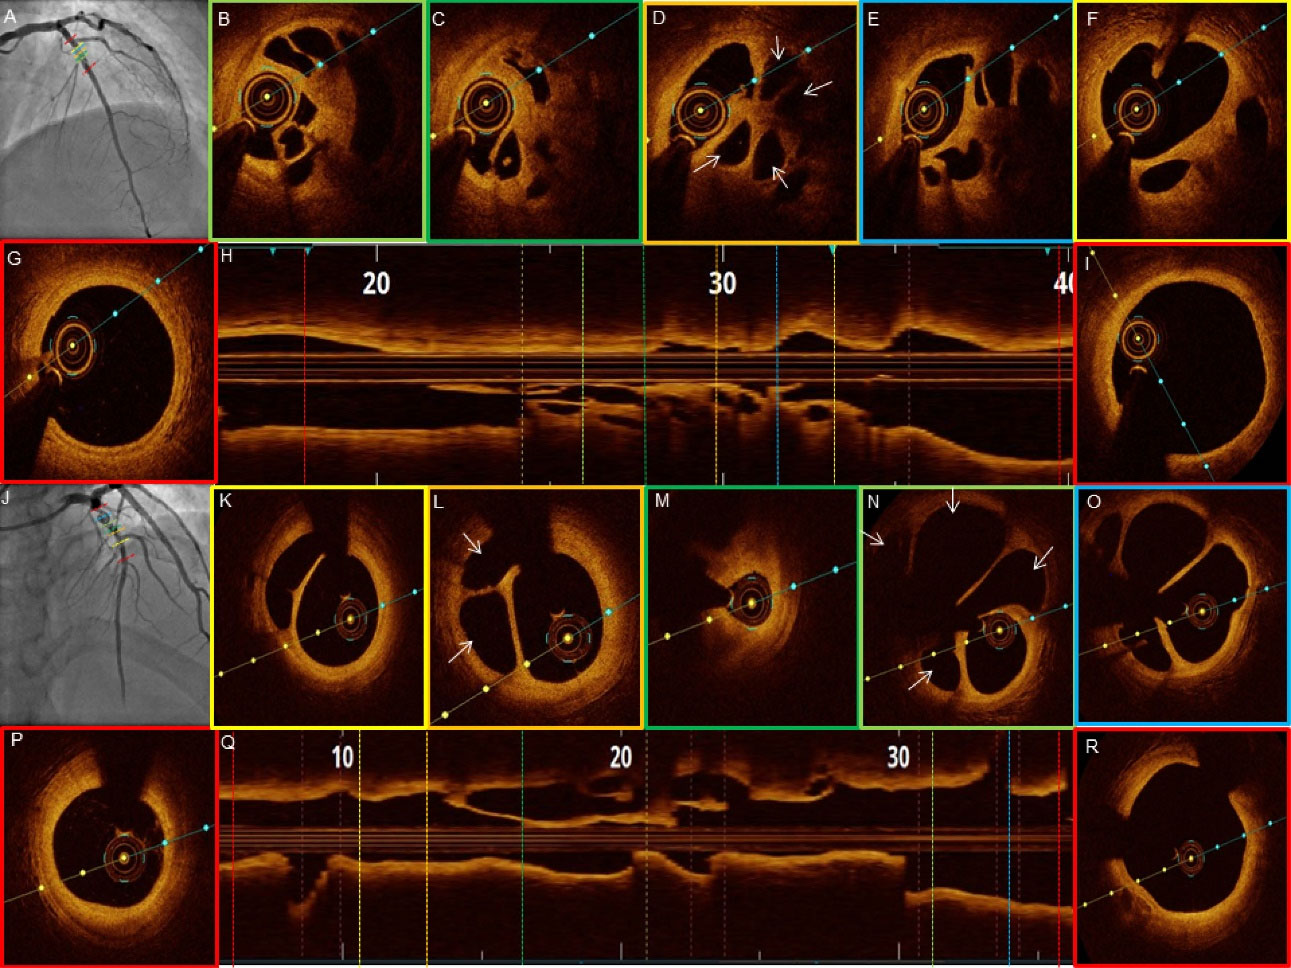

jcvtr-14-220-g001

Figure 1. Angiographic patterns of recanalized thrombus. Panel (A-H) images corresponds to the patient #1-8. Veiled appearance (A, C and H). Pseudo-dissection (B and D). Braided like (E and F). Near occlusion (G).

jcvtr-14-220-g002

Figure 2. OCT images of patient #1-2 (RCA and LAD). Veiled appearance and pseudo dissection angiographic images respectively (A and J). (D) Small cavities (white arrows) and catheter fiber (yellow arrow). (N) Small cavities (white arrows). (E) Cholesterol crystals (blue arrow). (F) Lipid rich plaque (white arrowhead).